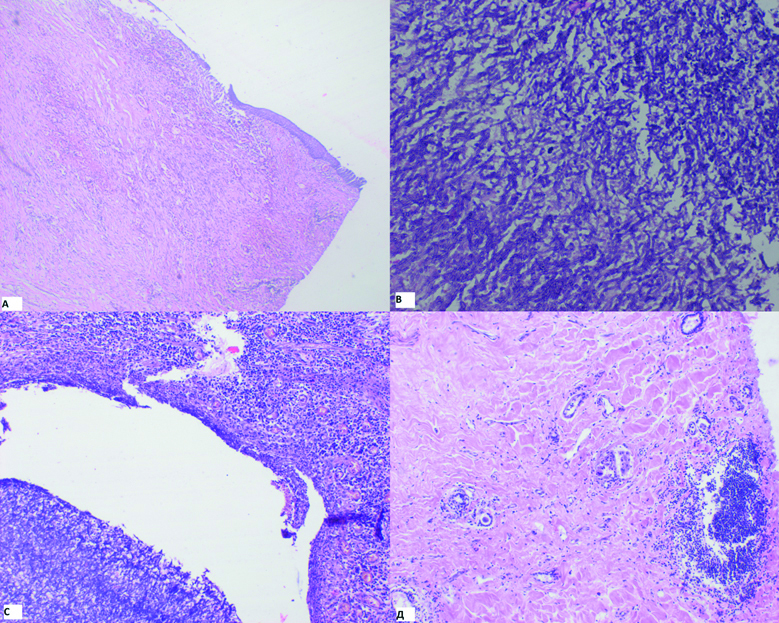

Histological findings in the surgical specimen of the removed lung: the specimen contains pulmonary tissue with focal sclerotic changes (Fig. 7А), loci of dystelectasis and atelectasis, inhomogeneous lymphohystiocytic infiltration of some of the interalveolar septa, in the perivascular and peribronchial areas, formation was seen of lymphohystiocytic sheaths with individual eosinocytes. In the lumen of a part of alveoli, there are old hemorrhages and accumulations of hemosiderophagi. There are sections of caseosis with signs of organization in the regular three-layer capsule, presence of multinucleated cells of Pirogov-Langhans and traces of leukocytes. Presence of perifocal granulomae of various age (Fig. 7D) with multinucleated cells of Pirogov-Langhans, no caseification. In the large focus of caseosis there is a large number of fungi druses (Fig. 7В, 7С), the capsule is represented with developing granulation tissue with moderate levels of macrophages and leukocytes and some eosinocytes. The pleura is with pronounced fibrosis and multi-phase granulomatous reaction of the epithelioid type with some leukocytes. The stump of the main bronchus is of normal structure without granulomatous reaction. Conclusion: picture of tuberculous inflammation in the pulmonary tissue with signs of development, formation of a mycetoma in one of the foci.

Figure 7. Histological picture of the surgical material: 7A – the wall of the chronic cavity, staining with hematoxylin and eosin, x 40.; 7B – multiple hyphae of the fungus Aspergillus in necrotic masses in the lumen of the cavity, staining with hematoxylin and eosin, x 200.; 7C – multiple hyphae of the fungus Aspergillus in necrotic masses in the lumen of the cavity, staining with hematoxylin and eosin, x 100.; 7D – a focus of fibrosis in the lung tissue, staining with hematoxylin and eosin, x 100.